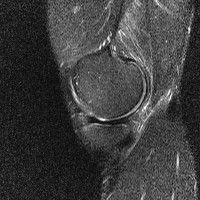

무릎 mri 간단히 봐주실 수 있으시나요 ㅠㅠ

안녕하세요 8년전 십자인대 수술하고 최근 무리한 운동에 무릎 불편감이 생겨서

mri 찍었습니다.

진단결과는 첫 찍은 병원에서 활액막염 이라는 진단을 받았습니다. 혹시 봐주실 수 있으실까요?

올라온 MRI가 단편적이라서 정확한 진단에 어려움이 있지만 십자인대에는 큰 이상이 있지는 않은것 같으며, 무릎관절내 물이 있는 것으로 보아 활액막염의 진단이 맞을 것 같습니다.

하지만 단편적인 영상이기 때문에 촬영병원에서 정확한 판독지 등을 받으시는 것이 좋겠습니다.